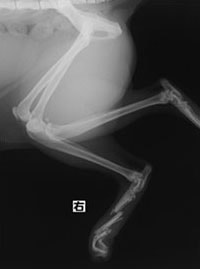

ペルシャ猫 11ヶ月齢 雄

他院にて左大腿骨遠位の成長板骨折(salter-harrisⅠ型)が認められており、治療相談を目的として来院。当院にて、キルシュナーワイヤーを用いたピンニングにより骨折部位の整復を行いました。術後の経過は良好で、現在も経過観察中です。

術前レントゲン

術後レントゲン